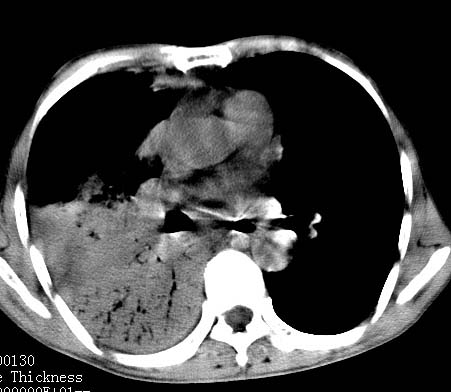

病人女 60岁 咳嗽 气促十余天,大叶性肺炎.

右肺上下叶均见 大片状密度增高影,边界清晰,其内可见支气管充气征,气管支气管通畅。纵膈略向右移位,其内无肿大淋巴结影。首先考虑炎性病变。不排除一些特异性的炎症。不知道发烧吗??wbc高吗??建议治疗后复查!!

看影响还是首先考虑炎性改变,建议实验室检查,还有要警惕炎性肺泡癌,具有的枯枝征象。

右肺感染性病变(大叶性肺炎可能);建议抗炎治疗后复查。

看影像还是首先考虑炎性改变,建议实验室检查,还有要警惕炎性肺泡癌,具有的枯枝征象